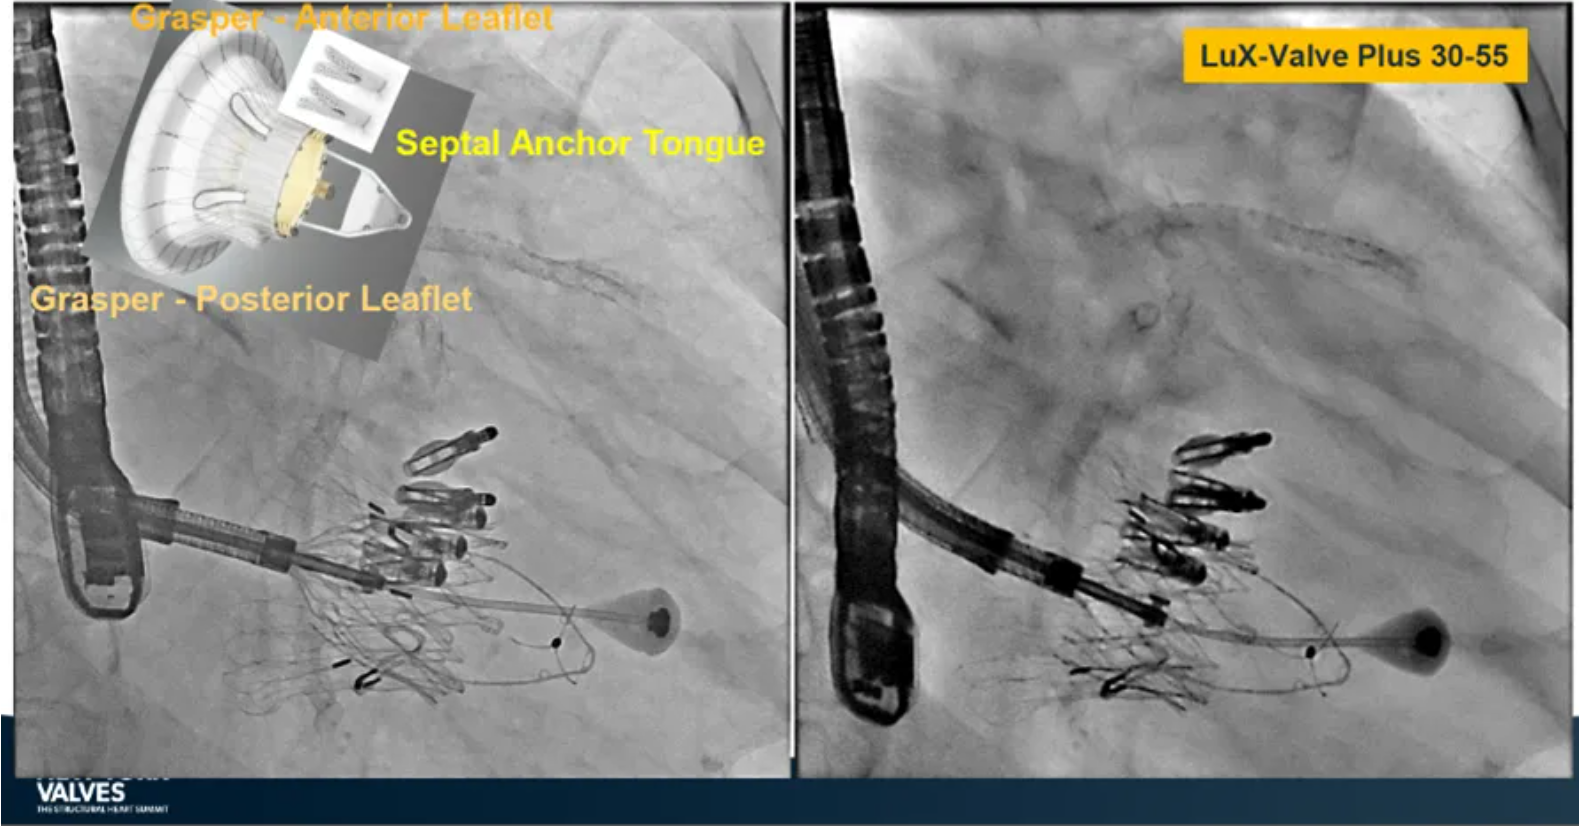

Granada教授表示,LuX-Valve Plus是一款不依賴于徑向支撐力固定的多功能TTVR器械,它的創(chuàng)新設(shè)計(室間隔錨定和瓣葉夾持件)提供了多樣的固定和穩(wěn)定技術(shù)。多中心臨床試驗研究TRAVEL II 展現(xiàn)了LuX-Valve Plus的安全性和有效性,能實現(xiàn)較短的器械操作時間,較低的復合事件發(fā)生率,并在6個月期時顯著降低三尖瓣反流等級,以及帶來心功能和生活質(zhì)量等指標上的明顯改善。

來自中國香港瑪麗醫(yī)院(Queen Mary Hospital, Hong Kong, China)的Simon Lam教授在2024紐約瓣膜會上分享了一例復雜案例,一名高齡男性患者在2年前行二尖瓣和三尖瓣TEER術(shù)式后繼發(fā)三尖瓣反流,遂再次行二尖瓣TEER術(shù)式和用LuX-Valve Plus行三尖瓣TTVR術(shù)式。

本次術(shù)式中,LuX-Valve Plus的植入緊隨二尖瓣修復術(shù)式之后,且并未取出前期植入的三尖瓣修復夾,這意味著LuX-Valve Plus在患者有過二尖瓣和三尖瓣修復夾植入情況下的兼容性,并且?guī)砹擞行У闹委熃Y(jié)果。此外,這不僅體現(xiàn)了LuX-Valve Plus可以與二尖瓣術(shù)式并行,更可以兼容三尖瓣原位的其他修復夾產(chǎn)品。

來自中國上海復旦大學附屬中山醫(yī)院的魏來教授在2024年臺北瓣膜高峰論壇上分享了他使用LuX-Valve Plus治療三尖瓣反流的經(jīng)驗。魏來教授闡述道,隨著療法演變,目前全球市場有以LuX-Valve Plus及其他產(chǎn)品為代表的經(jīng)導管三尖瓣介入置換系統(tǒng),逐漸成為重度三尖瓣反流的一線治療方案。他介紹到,LuX-Valve Plus創(chuàng)新的室間隔錨定和經(jīng)頸靜脈入路的方式,能夠帶來安全穩(wěn)定的錨定效果及較短的輸送行程;其可調(diào)彎的輸送系統(tǒng)能保證同軸性,從而快速和安全地將人工瓣膜送達目標手術(shù)區(qū)域,有效降低入路周邊解剖組織并發(fā)癥及術(shù)中出血風險。